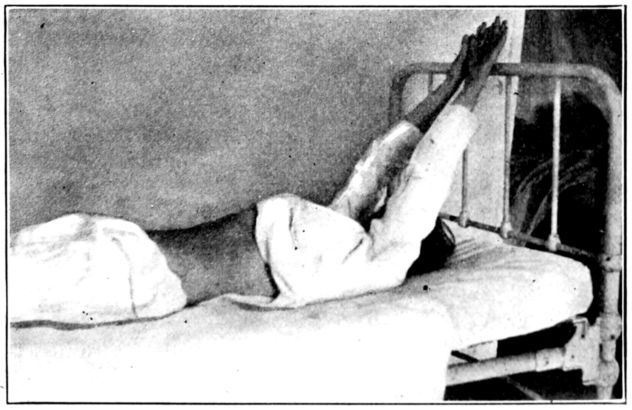

| 129, 130, 131, 132, 133, 134, 135. | Bed exercises taken during the puerperium | 350 to 353 |